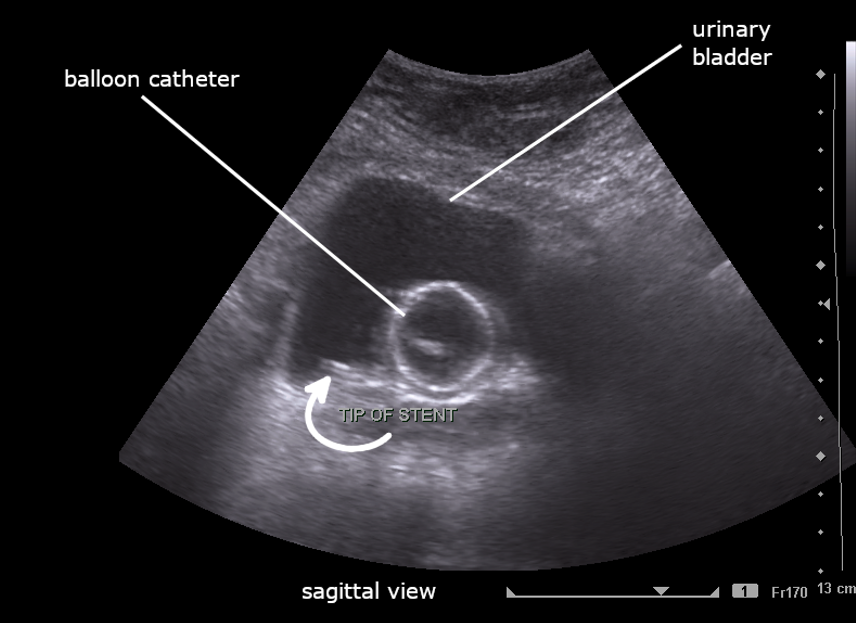

Foley balloon mispositioning

If the Foley catheter is not visualized within the bladder lumen, it may be mispositioned outside the bladder, in the urethra, or in adjacent structures, which could interfere with proper drainage and function (Figure 16).

Figure 15: Distended bladder despite Foley catheter in situ, suggesting the catheter is clamped or obstructed. Video courtesy of Dr. Dave Kirschner, used with permission.

Figure 16: Sagittal image of the bladder with foley catheter in the urethra. Image courtesy of Dave Kirschner, used with permission.

Figure 13: Sagittal image of partially filled bladder with Foley catheter. Image By Cerevisae – CC BY-SA 4.0 license.